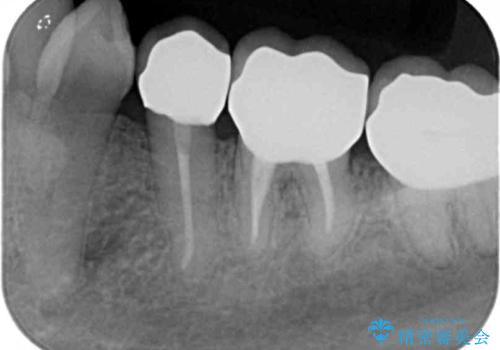

- 違和感や疼きのある左側小臼歯に加え全体的にクラウンや詰め物のやりかえを希望され来院されました。

治療後に再発した虫歯や根管再治療に加え、穴の空き症状のある上顎左側小臼歯は抜去を行いインプラントによる機能回復治療を計画します。

X線写真検査ではわからない虫歯も外してみると再発していることがあります。虫歯を丁寧に取り除き、再発を防ぐべく精密なクラウンの作製を行うことが長期的な予後につながります。